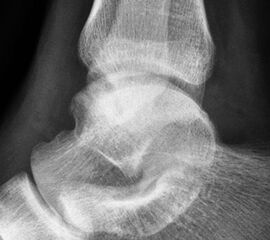

- Röntgenaufnahme des OSG in 2 Ebenen (seitlich und Mortiseview).

- MRT des OSG zur Beurteilung des ligamentären Schadens und möglicher Knorpelläsionen.

- Ggf. CT zur Bestimmung der Lage und Größe begleitender Osteophyten oder freier Gelenkkörper, sofern diese als Begleitpathologien vorliegen.